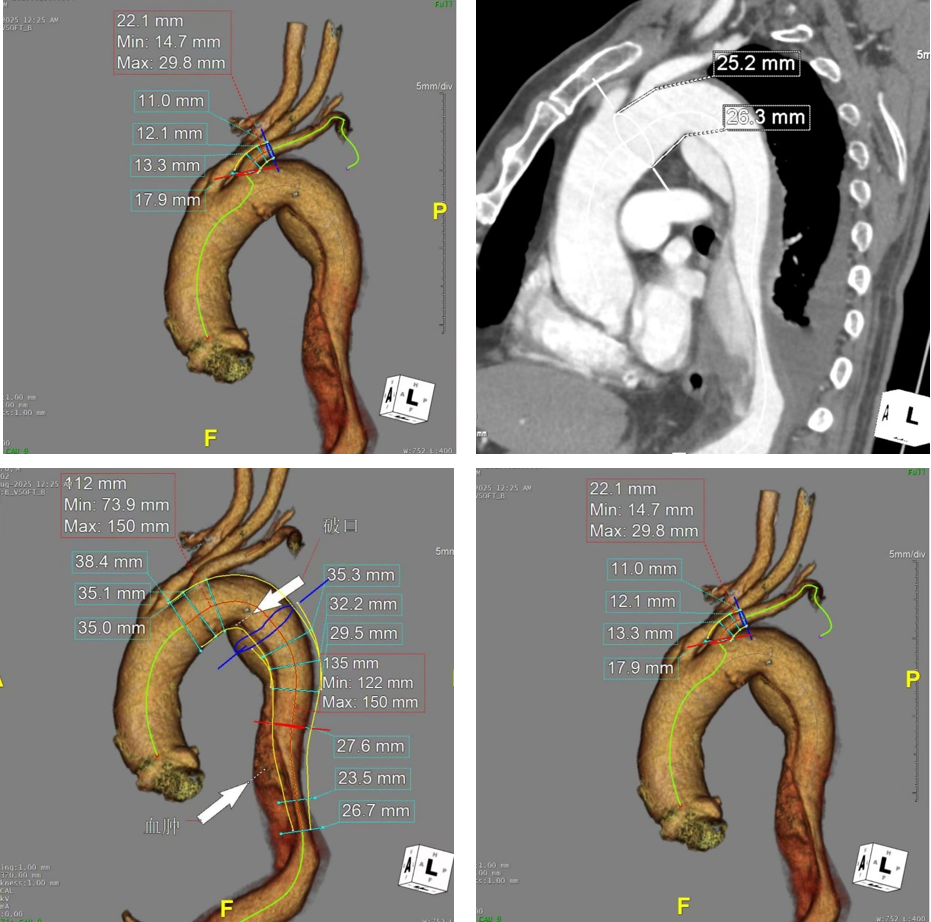

CASE 2:Ⅲ型弓溃疡伴Stanford B型夹层

患者资料:男性,70岁,因脑梗死入院后行CTA发现Stanford B型夹层,破口位于左锁骨下动脉后缘平面,伴局部溃疡。

手术过程

造影明确破口位置后,先释放远端主体支架。

随后释放近端分支支架主体,使内嵌孔道对准左锁骨下动脉。

导入分支支架,造影显示主体支架顺应成角弓形,分支支架贴合锐角发出的左锁骨下动脉,隔绝良好,无内漏。

体会

该病例弓部成角锐利,但TBE支架的柔顺性表现出色,分支支架顺利通过弯曲血管且无折缩。分支支架导入时略有卡顿,采用球囊或导管辅助推送可顺利通过。建议在分支支架释放后行球囊后扩,优先选择柔顺性好的非限制性球囊(如腹主动脉球囊),以避免硬球囊扩张时导致支架移位。